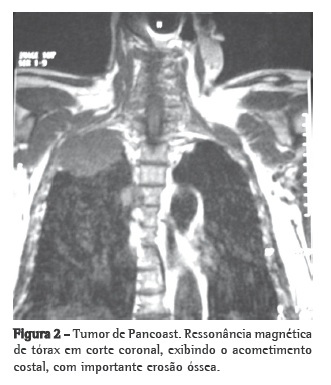

Após dois anos, o paciente foi enviado ao nosso ambulatório com exames de imagem mostrando alterações císticas, nódulos e pneumotórax de médio volume à direita. Optou-se por drenagem pleural com expansão total do pulmão e retirada do dreno. Além disso, realizou-se prova de função pulmonar, a qual mostrou grave distúrbio obstrutivo (volume expiratório forçado no primeiro segundo de 37% e capacidade vital forçada de 50% do valor predito). Vinte dias após a retirada do dreno, o paciente apresentou um novo episódio de pneumotórax à direita (Figura 2), e, nesse momento, optou-se pela realização de drenagem pleural seguida de expansão de pleurodese em razão da impossibilidade de se ressecar todas as metástases, já que isso envolveria uma grande ressecção de parênquima pulmonar em um paciente com baixa reserva pulmonar. Após oito meses, o paciente apresentou quadro de escarro sanguinolento, culminando em hemoptise de médio volume, que tanto a broncoscopia como a arteriografia mostraram originar-se no brônquio lobar superior esquerdo (metástase escavada), e não houve sucesso na contenção do sangramento por esses métodos. Optou-se pela realização de lobectomia superior esquerda associada à ressecção de duas metástases localizadas em lobo inferior esquerdo (Figura 3). O paciente recebeu alta após seis dias e permaneceu em acompanhamento ambulatorial.